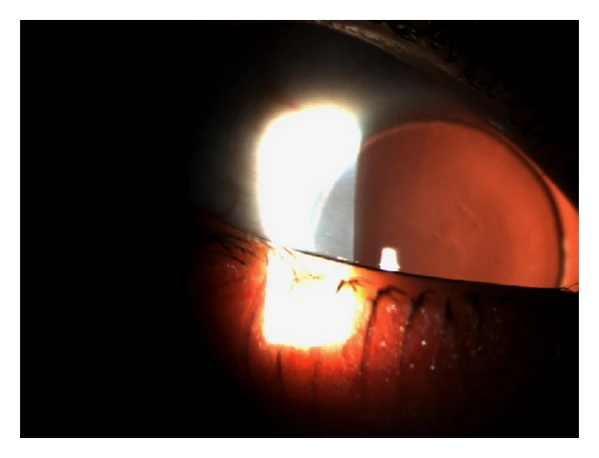

- биомикроскопию за щелевой лампой — исследование позволяет оценить края век, состояние слёзных точек, ресниц, конъюнктиву, роговицу, характер помутнений хрусталика;

- врождённая катаракта;